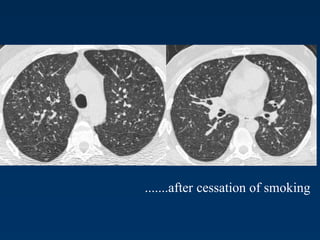

Langerhans Cell Histiocytosis

Differential Diagnosis

Only small nodules

Sarkoidosis, Silikosis

Only cysts

idiopathic Fibrosis

LAM

Destruktive emphysema

A professional diver.............

.......after cessation of smoking